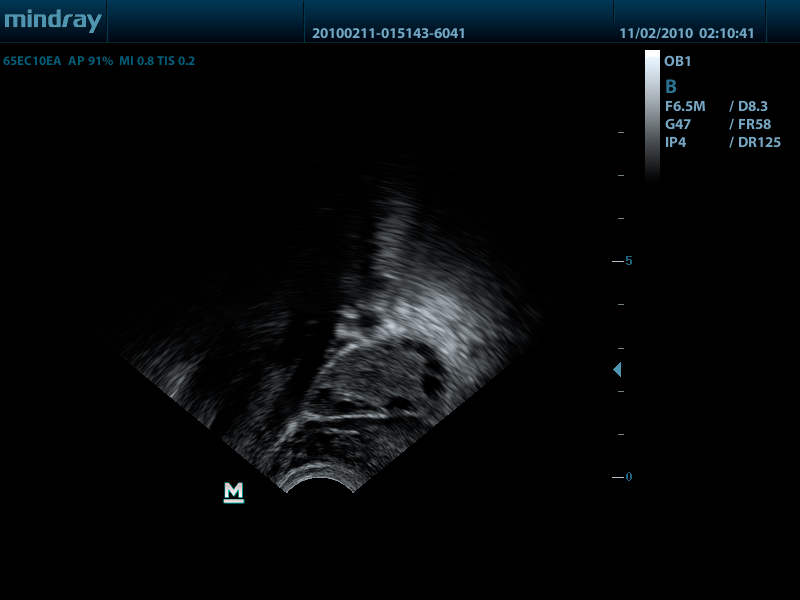

Внутриполостной датчик 65EC10EA (5.0/6.5/7.5/8.5/Н8.0/Н9.0 МГц, R-10 )